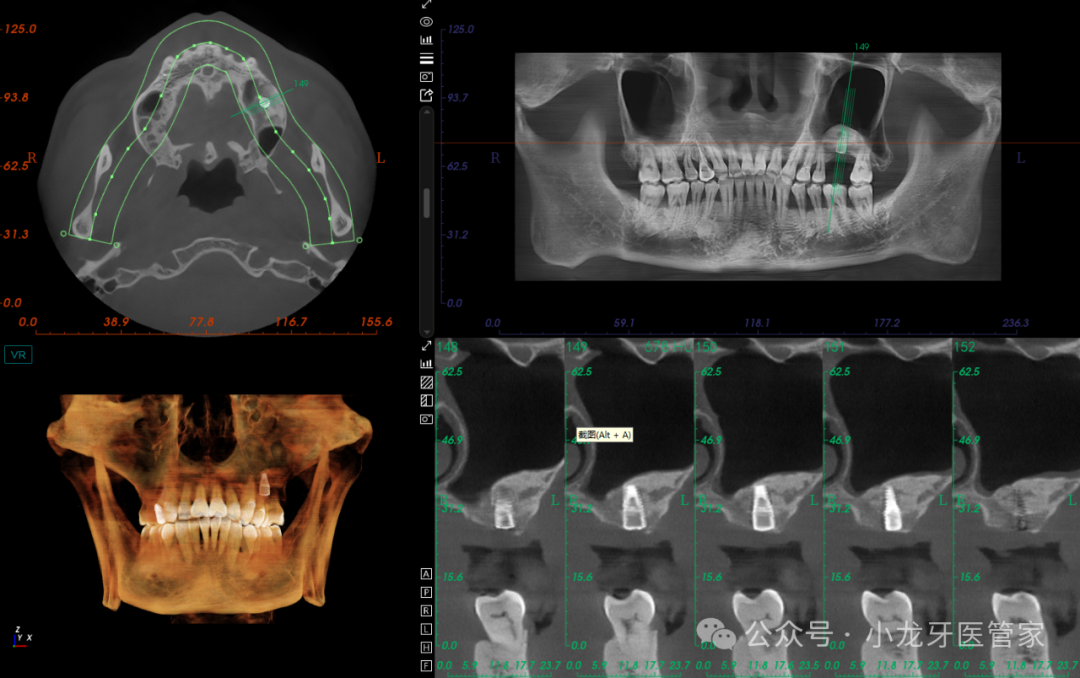

患者知情同意并签署《口腔种植修复知情同意书》。常规消毒铺巾,4%阿替卡因局部浸润麻醉,26缺牙区牙槽嵴顶作水平切口,全层切开粘骨膜,翻瓣,发现缺牙区骨面平坦,整体骨质较硬(III类骨),定位,先锋钻备洞至预定深度,扩孔钻逐级扩孔,制备种植体窝,置入ITIblt骨水平种植体,型号:4.8mm*10 mm,植入扭矩35N.cm,旋入覆盖螺丝。减张缝合。

术后影像学图片